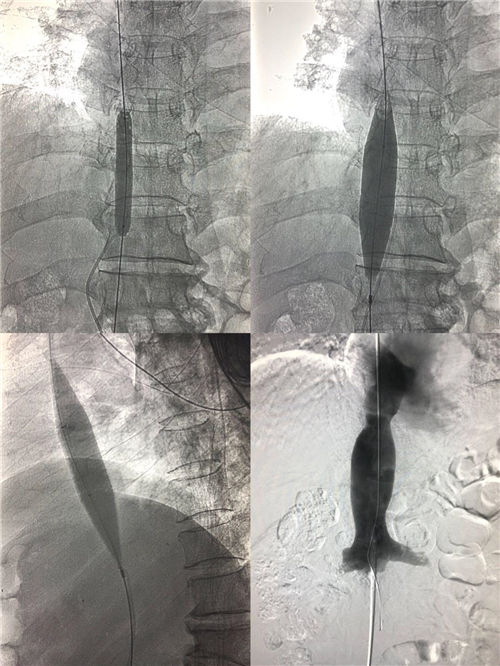

8月31日早8:15,介入科李建国主任、何彤副主任在局麻下对患者实施了经右侧颈静脉、右侧股静脉上下入路穿刺,对端造影,利用导管导丝成功打通下腔静脉闭塞段。再选用不同型号球囊分次扩张,在全体医护人员的密切协作努力下,闭塞的下腔静脉终于通畅,手术历时1小时15分钟,患者生命体征平稳安返病房,进一步的康复中。

布-加综合征首选介入手术治疗,该手术是介入医生在DSA的透视监视下利用穿刺针、导管导丝、球囊等一系列器材对患者进行的微创治疗,手术能迅速打通下腔静脉闭塞段,显著降低下腔静脉回流右心房的阻力,可有效减少食管胃底静脉曲张再出血和腹水复发等肝硬化并发症,使患者下肢溃烂得到逐步改善。手术时间短,不需开刀,患者全程清醒无痛苦,创伤小、效果好,能为此类患者快速有效解除病痛折磨。